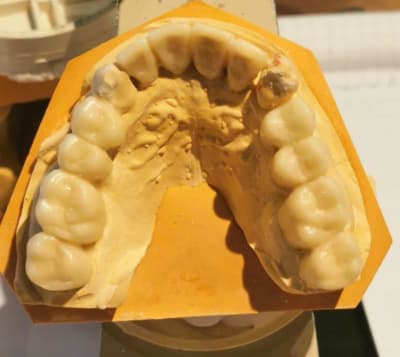

une idée du wax pour le maxillaire, mais ça ne me plait pas trop...

--

à faire le provisoir

dents un peu grosses?

courbe un peu plate...je reflechis